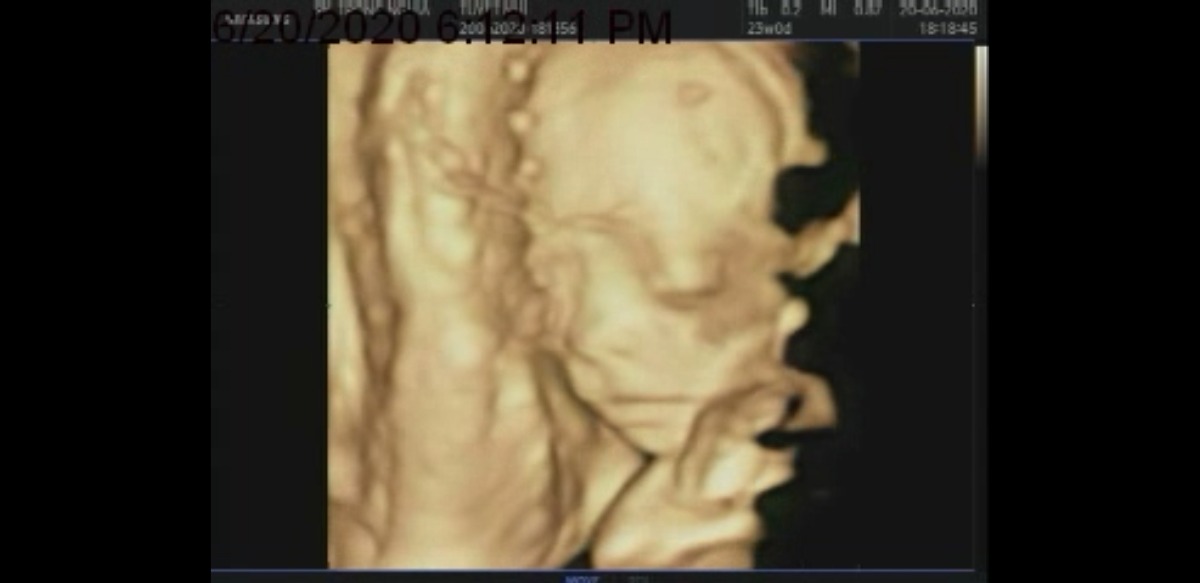

Các Mom cho em hỏi lúc 22w em siêu âm bệnh viện bác sĩ bảo em bé phát triển bình thường. Nhưng 23w3d em siêu âm 4D ở phòng khác tư khác thì bác sĩ nói chỉ số em bé chỉ bằng 22w, nằm ở bách phân vị thứ 10 của tuần 23w thì có sao ko ạ? Em tập đầu nên hơi lo ạ. Và cho em hỏi ăn uống như thế nào để vào con ạ? Em.cảm ơn các mom.

Dạ em có hỏi nhưng bác sĩ chỉ nói là các chỉ số tương đường tuần 22w. Và ko trả lời gì thêm cũng ko dặn dò gì thêm ạ. Em xem kết quả siêu âm so với tiêu chuẩn bé theo tuần thì thấy cũng hơi nhỏ hơn xíu ạ. Bằng với kết quả siêu âm tuần 22w em siêu âm ở bệnh viện. Em ko biết có phải do em siêu âm gần nhau quá mà lại ở 2 nơi khác nên có sự khác nhau.ko ạ?